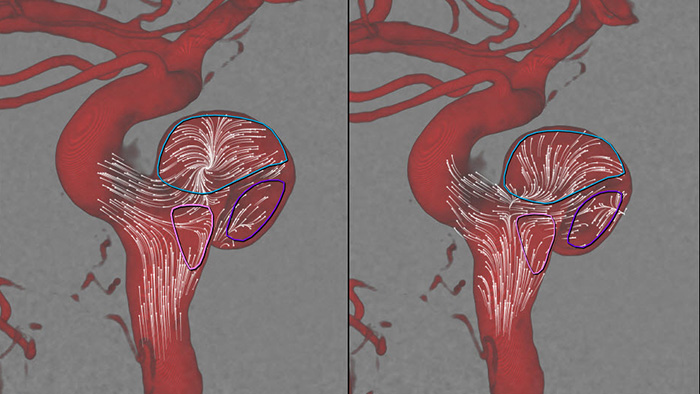

SmartCT Angioでは、数秒で3D再構成でき、動脈瘤と血管との位置関係、形状、サイズ、重症度を評価し、治療のためのターゲットアングルの決定を支援します。3D画像は高い空間分解能と患者の体動を自動補正して再構成表示します。